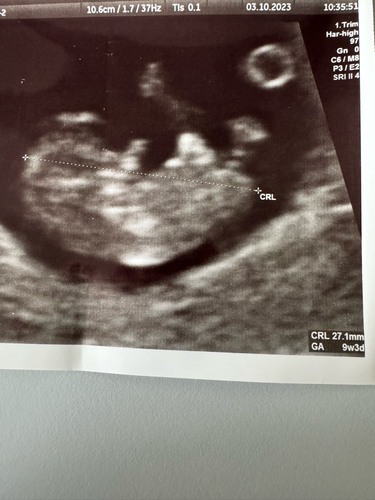

Deze was rond 8+4. Vroeger dan de vorige foto maar scherper beeld door ander echo apparaat!